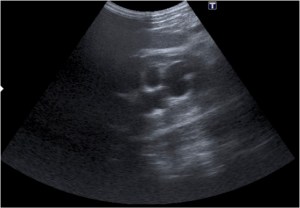

Tras el tratamiento de la recidiva y nefrostomía para la hidroureteronefrosis, vuelve acudir al hospital a los 9 meses por episodio de dolor en FD y malestar general. Se realiza una ecografía de urgencias.

Se realiza nueva TC bifásico abdominopélvio y Uro TC.